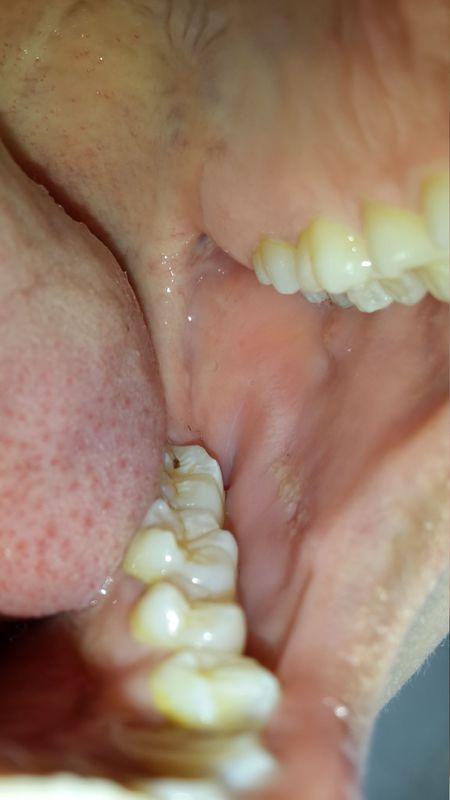

口腔咬合线发白突起是何问题?

- 颜色: 表面呈白色或淡黄色的假膜覆盖,看起来是“发白”的。

- 形状: 通常是圆形或椭圆形的凹陷,像一个“小坑”或“火山口”。

- 突起感: 您感觉到的“突起”可能不是溃疡本身,而是溃疡边缘的黏膜组织因为炎症而略微肿胀、隆起,形成一个有边界的凹陷区域。

- 周围情况: 溃疡周围黏膜充血发红,边界清晰,通常对应着上或下牙齿的咬合痕迹。

想象一下,在您脸颊内侧的咬合线上,有一个硬币大小的圆形区域,这个区域的中心是凹陷的,上面覆盖着一层薄薄的、像白色奶油一样的物质,这就是假膜,这个凹陷的边缘是微微隆起的红色组织,整体看起来就是一个“红圈白心”的“小坑”,您用舌头去舔,会感觉到一个明确的凹陷和边缘的凸起,并且会感到疼痛。

您描述的“口腔咬合线发白突起”,最有可能的是咬伤引起的创伤性溃疡,但也不能排除白色念珠菌感染或更严重的口腔白斑,请对照上述描述进行初步判断,如果情况不严重或明确是咬伤,可以尝试家庭护理并观察,如果出现任何“警报信号”或自己无法判断,请务必及时就医,早诊断、早治疗是关键。